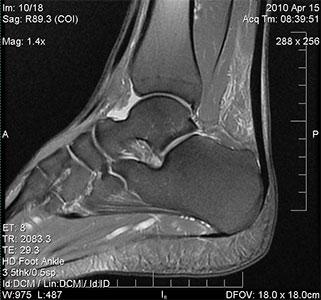

- Методы диагностики: Кроме УЗИ и МРТ, могут быть также использованы рентгенография и анализы крови для выявления воспалительных маркеров.

Главные симптомы включают боль, отечность и изменение цвета кожи в области сустава. Воспалительный процесс приводит к нарушению функций ноги, что проявляется хромотой. Для подтверждения диагноза требуется дополнительные исследования – рентгенография, УЗИ, пункция сустава, МРТ.

Диагностика заболевания

Лечение синовита голеностопного сустава начинается лишь после того, как диагноз будет подтвержден. Для этого применяют следующие методы диагностики:

При значительном отеке тканей провести оценку состояния сустава бывает непросто, поэтому может потребоваться дополнительно УЗИ, МРТ или рентгенографическое исследование.

Инструментальные методы

Пункция сустава

Пункция позволяет не только получить образцы внутрисуставной жидкости для анализа, но и осуществить лечебные мероприятия. С помощью этой процедуры врач может оценить состояние синовиальной жидкости и удалить излишки жидкости из сустава, что облегчит симптомы.

Лишь подтверждая диагноз, врач сможет выбрать наиболее подходящие методы лечения.